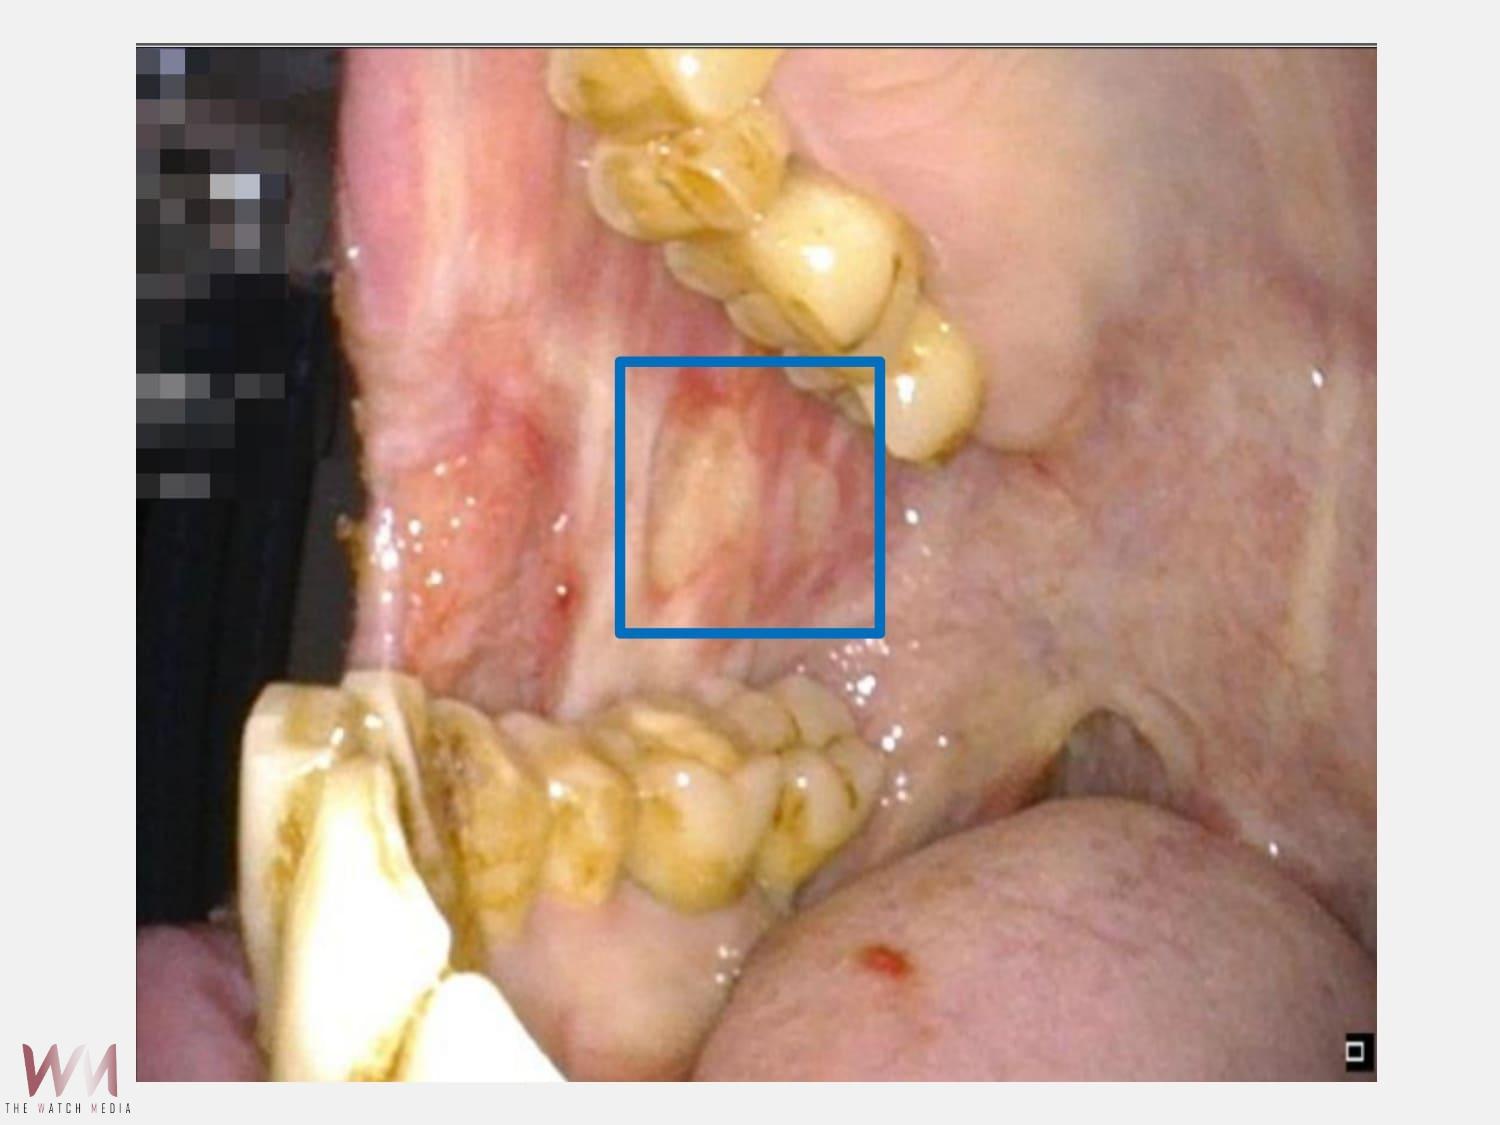

(觀傳媒中彰投新聞)【記者廖妙茜/台中報導】52歲的孫先生罹患口腔癌,到仁愛長庚合作聯盟醫院(大里仁愛醫院)經由耳鼻喉科醫師評估過後得知切除腫瘤後將會產生大面積的軟組織缺損,甚至骨骼外露,不只口腔的功能及外觀大受影響,自信心也一落千丈。因此,孫先生便至整形外科郭曉芮醫師門診求診,由該科團隊與耳鼻喉科同步規劃切除和重建,依缺損條件客製化設計皮瓣厚薄及形狀,兼顧其傷口閉合與口腔功能恢復,終於在術後能夠敞開心中大門,重新擁抱人群。郭曉芮醫師指出,頭頸癌重建把設計好的游離皮瓣像量身訂做的拼圖一樣放回去,確保病人治療及生活不中斷,關鍵在於不只是把缺損「補起來」,而是讓病人能吞嚥、能發音,恢復社交與自理能力。